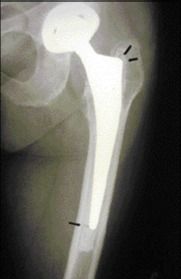

Technique Technique de reconstruction par greffe morcelée impactée et treillis métallique au cours des révisions fémorales d'arthroplastie de hanche , Henri Migaud Service d’orthopédie II, Hôpital Roger Salengro, Place de Verdun, Lille, France 🖂 hemigaud@norndet.fr , Antoine Duquennoy Services de Chirurgie Orthopédique, Hôpital Salengro, CHRU de Lille, Lille, France N°102 - Mars 2001 ● 14 min de lecture